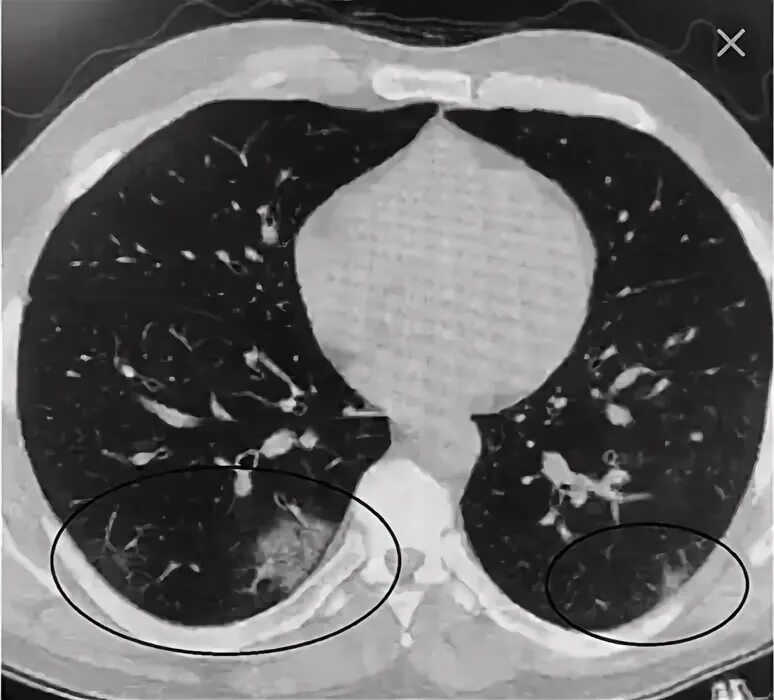

Кт после ковид